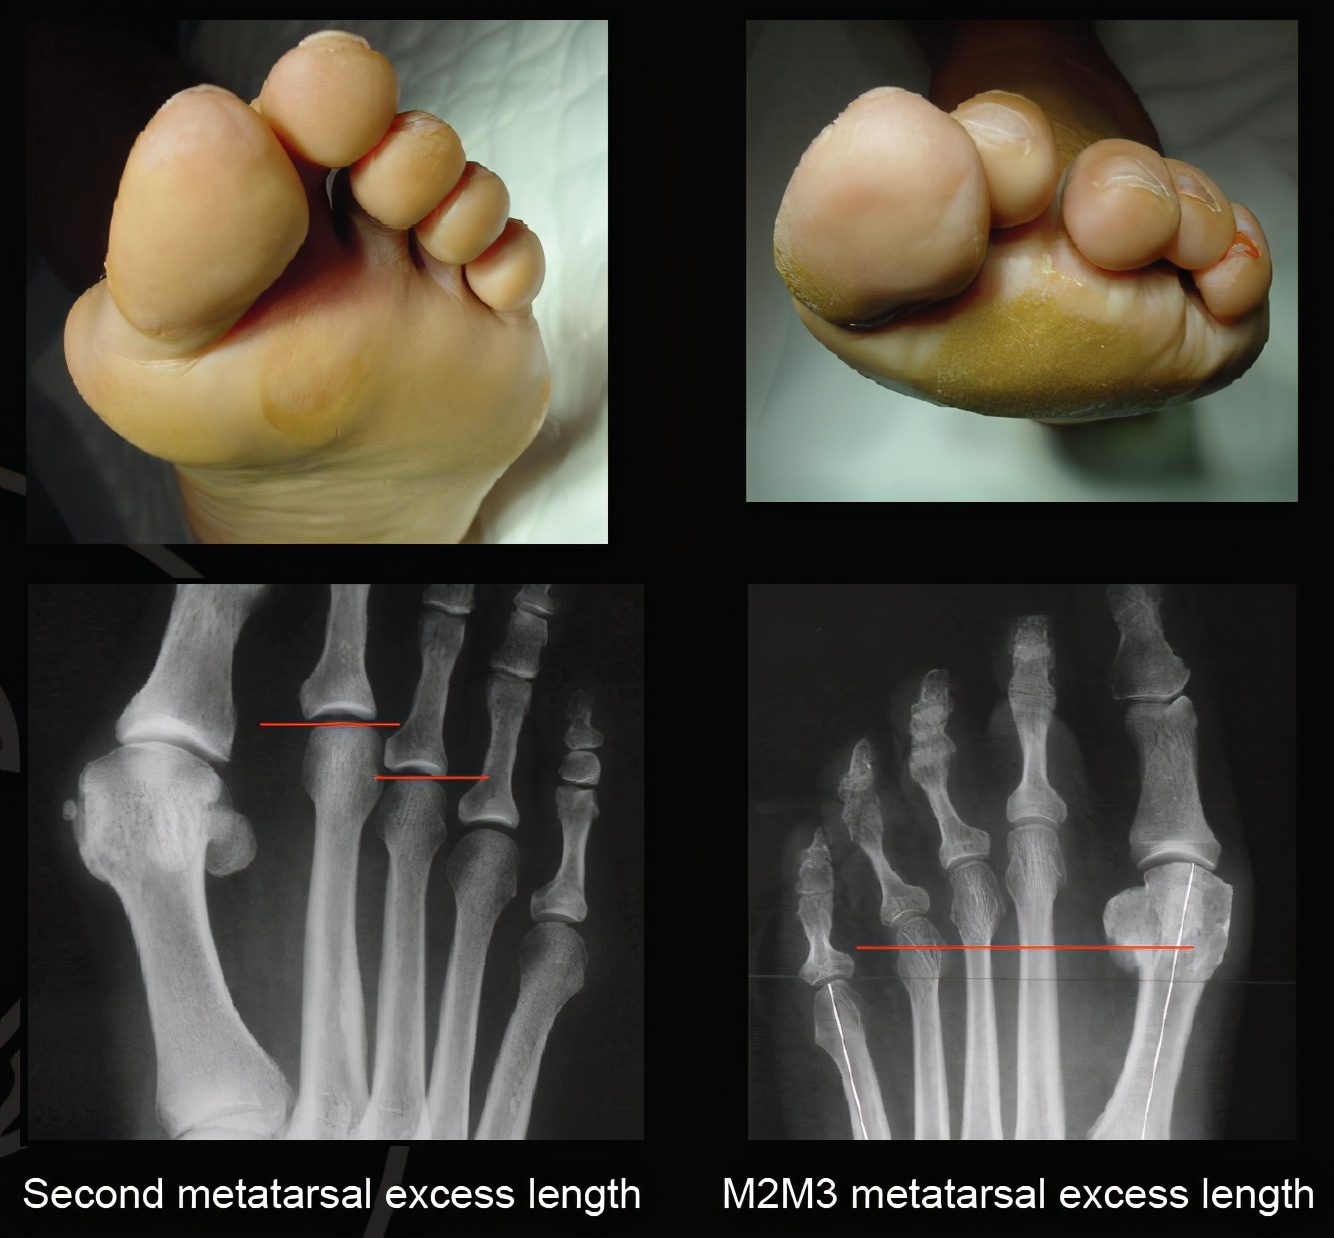

前足茧子与跖骨的关系

导致前足长茧子主要有几个因素,比方说拇外翻导致前足足横弓塌陷;比方说跖骨长短不协调,上图这个案例就是典型的跖骨长短不协调导致的第二三跖趾关节下方长茧子。

前足的负重主要有第一跖趾关节负重,然后合并前足的足横弓这个特点,就能负责弹跳及日常负重等情况。我们可以看到第一跖骨明显比其余跖骨要粗大,而且第一跖骨下方还有起缓冲作用的籽骨。当第一跖骨过短的时候,或者因为拇外翻导致第一跖骨上抬的时候,原本应该由第一跖骨承受的重力转移到了第二跖趾关节,尤其是图一那种第二跖骨绝对长度较长的朋友们,其第二跖骨会抢着来承受重力,而第二跖趾关节本来设置的时候并不能承受如此重力,第二跖趾关节为了更好承受重力,就只有增加受力面积,这就是第二跖趾关节下方长茧子的原因,讲到这里,你有明白了吗?